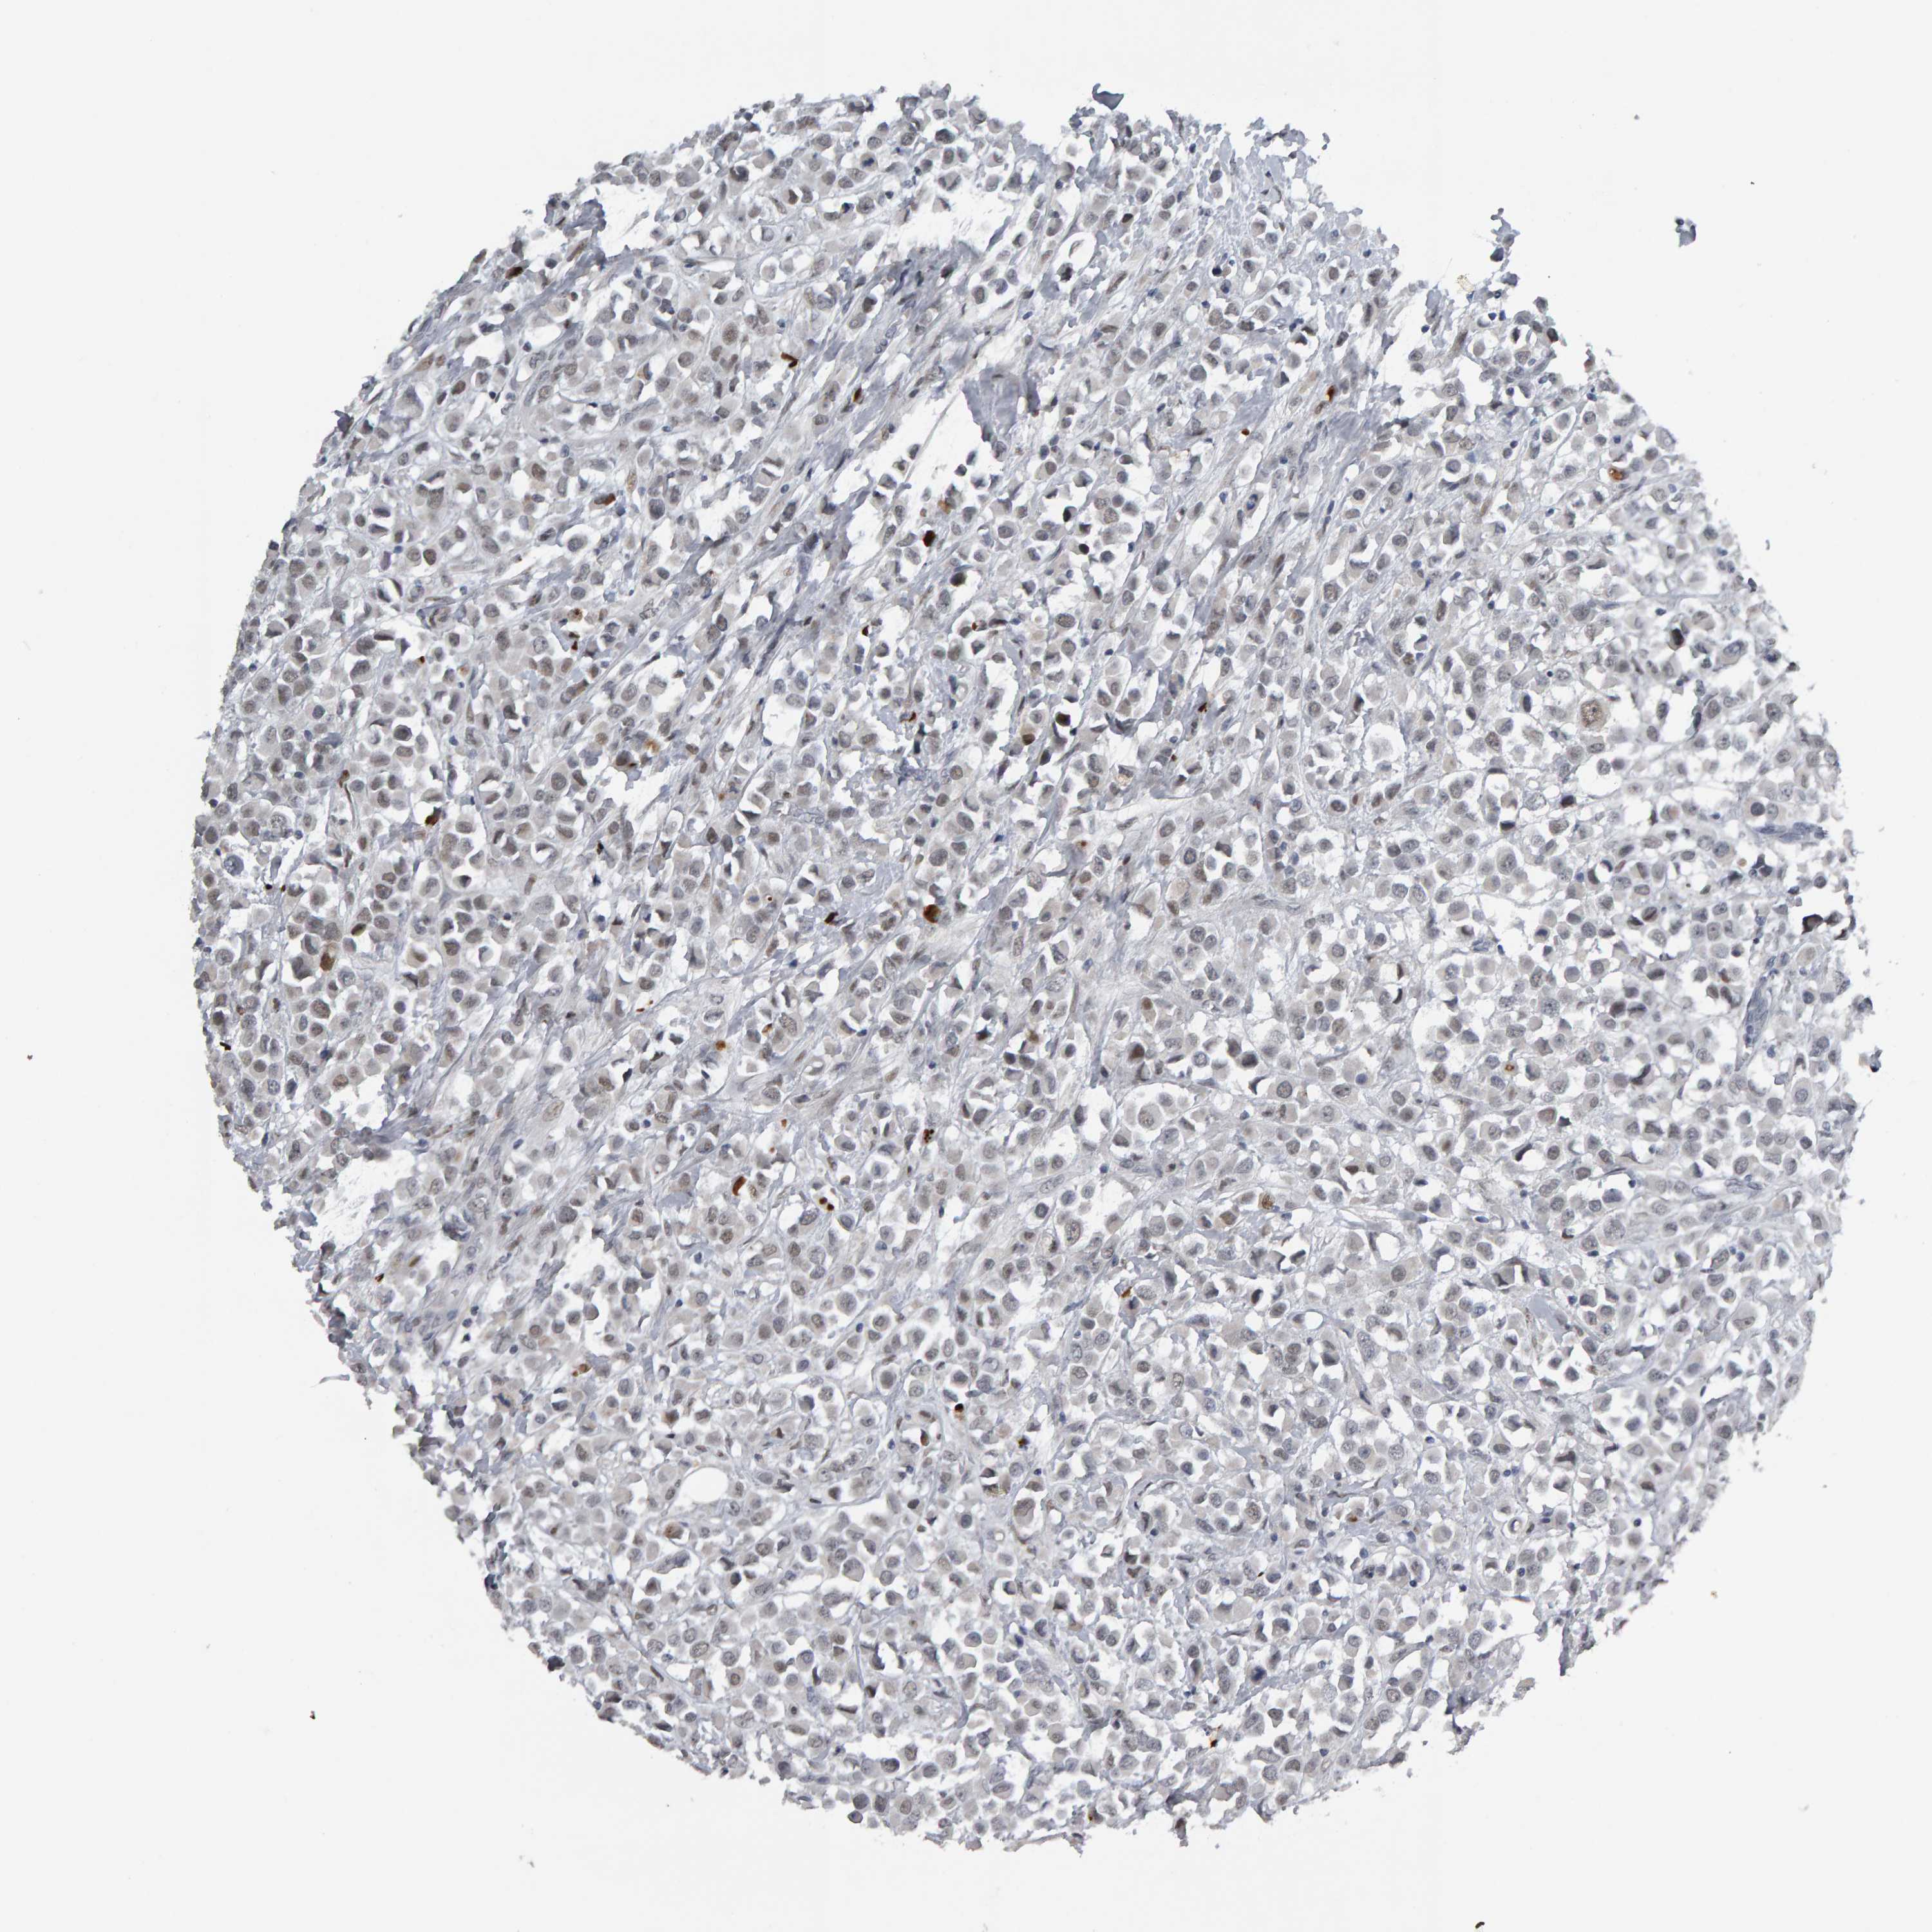

CANCER BREAST CANCER Show tissue menu

BRCA TCGA BRCA VALIDATION PROTEIN EXPRESSION